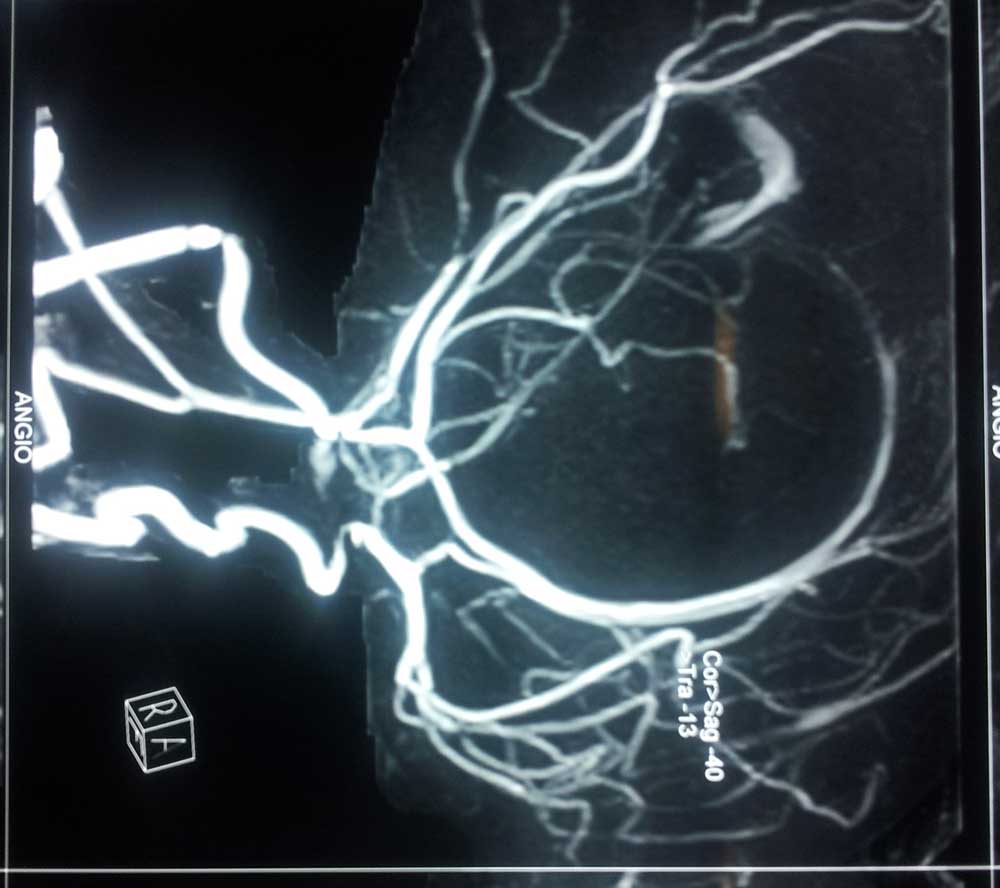

MRA

• MRA